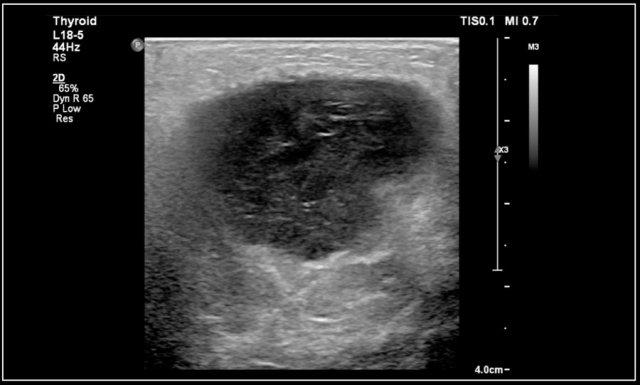

Nang ống giáp lưỡi có thể không có âm vang hoặc giảm âm vang với các tiếng vang bên trong, do nhiễm trùng, xuất huyết hoặc thành phần chứa protein.

Phần lớn nang ống giáp lưỡi nằm trong vòng 2 cm so với đường giữa.

Đây là hình ảnh cắt ngang của một nang ống giáp lưỡi giảm âm có một số tiếng vang bên trong nằm ở đường giữa.